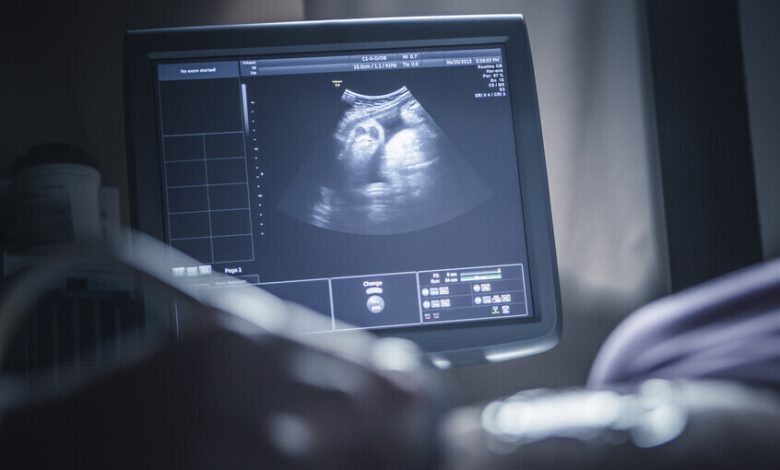

ولد طفل في الهند بحالة طبية غريبة ونادرة للغاية، حيث كان يحمل بداخله جنينين آخرين. وهذه الظاهرة تعيد تعريف فهمنا لتطور الأجنة وتُظهر تعقيدات قد تكون مختبئة داخل رحم الأم. وفي الشهر الماضي، زارت امرأة تبلغ من العمر 32 عاما في الهند مستشفى محليا لإجراء فحص روتيني أثناء حملها في الأسبوع الخامس والثلاثين. وعلى الرغم من أن فحوصاتها السابقة كانت طبيعية، اكتشف الأطباء “هيكلا إضافيا يحتوي على عظام” في بطن الجنين الذكر. وأظهرت فحوصات إضافية وجود جنينين آخرين مشوهين داخل بطن الجنين.وتعرف هذه الحالة النادرة باسم “جنين داخل جنين” (fetus in fetu)، وقد سُجلت نحو 200 مرة فقط في الأدبيات الطبية. ولا يعرف بالضبط عدد الحالات التي تضمنت أجنة متعددة.ووضعت المرأة مولودها في الأول من فبراير بعد نحو 35 أسبوعا من الحمل، وقام الأطباء بإزالة الجنينين، اللذين توقف نموهما في مرحلة ما أثناء الحمل، من بطن الرضيع.ووفقا لتقارير محلية، فإن الأم والطفل بصحة جيدة، في حين أن الجنينين الآخرين كانا غير مكتملي النمو لدرجة تمنع بقاءهما على قيد الحياة.ومن غير الواضح بالضبط ما الذي يسبب حالة “جنين داخل جنين”، لكن الأطباء يعرفون أنها تحدث بشكل عام أثناء التطور داخل الرحم في حالات التوائم المتطابقة. ويحدث التوائم المتطابقة عندما يتم تخصيب بويضة واحدة بواسطة حيوان منوي ثم تنقسم إلى جنينين منفصلين.ويعتقد الأطباء أنه في حالات “جنين داخل جنين”، لا تنفصل البويضة بالكامل، فيعلق أحد التوأمين داخل الآخر وقد يستمر في تطوير ملامح مثل الأظافر والشعر والأطراف. وفي هذه الحالة، يرجح أن بويضة المرأة كانت تحاول الانقسام إلى ثلاثة أجنة ولم تنفصل بالكامل، ما أدى إلى جنين واحد قابل للحياة وجنينين داخل الجنين. ويعتبر الجنينان “طفيليين” (parasitic) لأنهما يعتمدان على الجنين المضيف للبقاء على قيد الحياة وليس لديهما أعضاء حيوية مكتملة النمو. وهذا يعني أنهما غير قادرين على الحياة ويجب إزالتهما.وهذه الحالة الجديدة هي واحدة من بين 8 حالات من أصل 10 حيث يتم احتجاز الأنسجة الجنينية الممتصة في البطن، ما يعطي الأطباء فرصة عالية لإزالتها دون الإضرار بالأم أو الطفل. وفي أحيان أخرى، تم العثور على أنسجة جنينية في فم الطفل، أو كيس الصفن، أو الدماغ.على سبيل المثال، في عام 2015، نجح أطباء صينيون في إزالة جنين تم العثور عليه في كيس الصفن لرضيع يبلغ من العمر 20 يوما. وفي حالة أخرى تم الإبلاغ عنها العام الماضي، عانت طفلة صينية تبلغ من العمر عاما واحدا من تأخر في النمو وزيادة في حجم الرأس عن المتوسط عندما اكتشف الأطباء جنينا ينمو داخل جمجمتها. وأظهرت الفحوصات كتلة طولها خمس بوصات في جمجمتها، أكبر قليلا من كرة البيسبول، وكانت تحتوي على قطع طويلة من العظام. وعلى الرغم من أن الأطباء تمكنوا من إزالة الجنين، إلا أن الطفلة عانت من تلف شديد في الدماغ وتوفيت بعد أقل من أسبوعين.